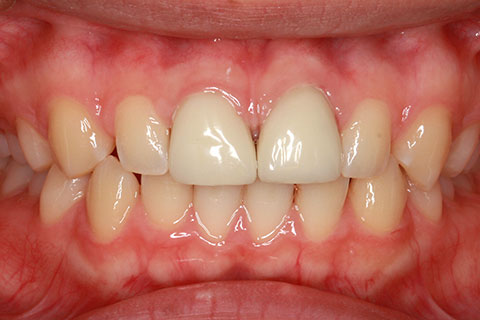

オールセラミックの症例1

上顎前歯のデコボコと色調を改善。

- 年齢・性別

- 40歳女性

- 治療期間

- 1ヶ月

- 抜歯

- なし

- 治療費

- 35.2万円

- 備考

- 前歯4本の変色歯及び歯列不正によるセラミック治療

- 治療内容

- 歯質を削除し、セラミック冠をセメント合着

- 施術の副作用(リスク)

- 知覚過敏、歯髄炎、荷重負担